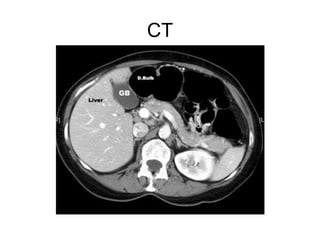

CT